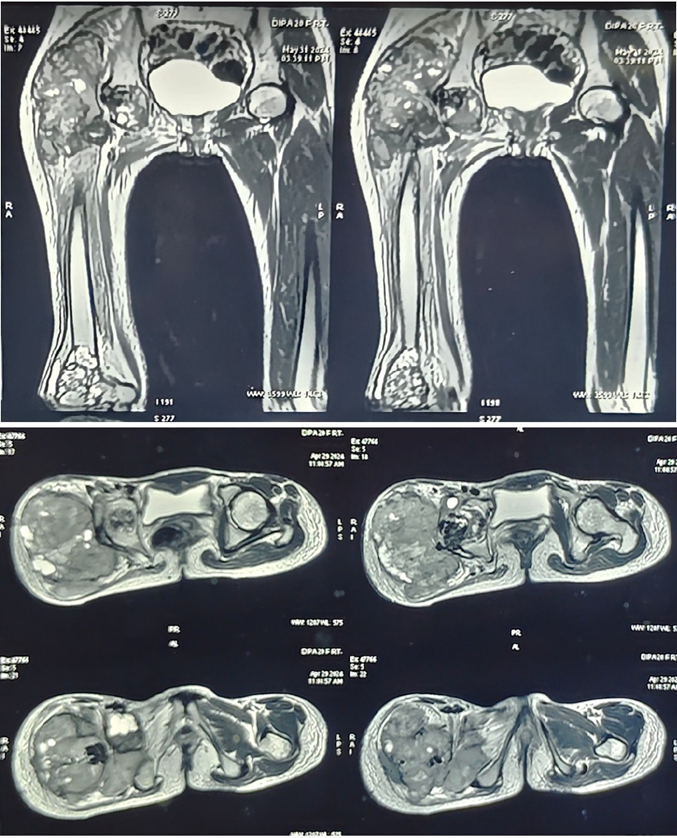

Magnetic resonance imaging (MRI) demonstrated a large, inhomogeneous, expansile, and infiltrative lesion measuring 12.3 × 14.9 × 12.1 cm, involving the right hip joint and surrounding periarticular tissues. The lesion infiltrated adjacent soft-tissue structures and caused significant erosion of the femoral head. Residual bone cement material was also evident, indicating recurrence (Fig. 3).

Figure 3: Magnetic resonance imaging showing a large tumor at the proximal femur, along with a skip lesion at the distal femur.